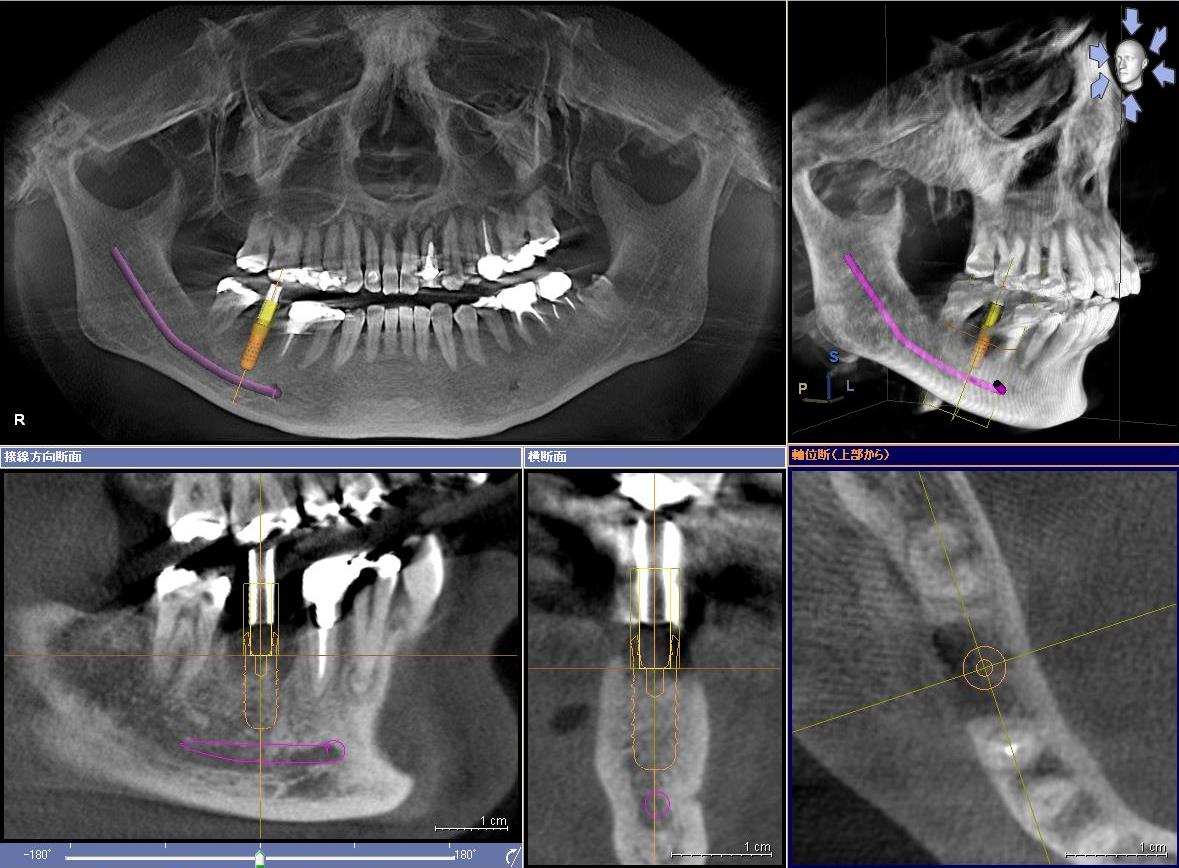

従来の二次元レントゲンでは捉えられなかった、立体的な顎の構造や神経の位置、病巣部位などを3次元的に映し出すことができる装置です。診断の精度向上によって、より安全な治療を提供することが可能になりました。インプラントや根管治療、親知らず抜歯など、幅広い治療に利用されています。